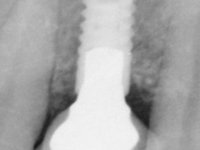

Paciente do sexo feminino, com 47 anos não fumadora. Apresentou-se na consulta com o dente 1.3 com tratamento endodôntico e com um espigão falso coto fundido, reabilitado com uma coroa provisória. Os dois incisivos laterais superiores são conoides e de reduzida dimensão. O dente 2.2 apresenta mobilidade, consentânea com uma significativa reabsorção óssea entre o dente 2.1 e o dente 2.3 Os dois incisivos centrais estão separados por um diastema de 3mm e o dente 2.3 apresenta uma oclusão cruzada com o dente antagonista. Verifica-se também a ausência de alguns dentes posteriores e uma higiene oral razoável. Na segunda intervenção realizada passados 8 anos, verificou-se que os incisivos centrais superiores se apresentavam cromaticamente mais escuros e apresentavam um sulco longitudinal no esmalte que estando pigmentado comprometia esteticamente o sorriso. O trabalho realizado na primeira fase do tratamento mostrava-se competente estética e funcionalmente. Por fim, um ano após a última intervenção, a paciente apresentou-se com uma fratura da faceta colocada no dente 2.1 provavelmente em resultado de estar em contacto com o coto do implante. A rigidez da anquilose implantar, pode ter sido a causa desta fratura. Outros casos deste tipo de fratura já foram observados por mim em situações clínicas idênticas. A faceta do dente 1.2 apresentava-se esteticamente comprometida e a própria estrutura dentária apresentava uma pequena cárie e, pelo que se recomendaria a sua substituição.

• Colocação de um Implante no local do dente 2.2. Reabilitação do implante com um “abutment” de componente coronário e gengival. em que o orifício de acesso ao parafuso fosse “camuflado” com uma faceta feldspática.

O tratamento iniciou-se com a re -preparação do coto do espigão falso coto fundido, com o objetivo de colocar as linhas de acabamento cervical com uma localização intra-sulcular e simultaneamente confecionar uma coroa provisória adaptada. Com um tratamento ortodôntico muito simples, fechou-se o diastema entre os incisivos centrais superiores e estabilizou-se esta posição com um arame colocado na superfície palatina dos centrais, funcionando como contenção. Posteriormente procurou-se fazer uma tração ortodôntica lenta do dente 2.2 com o intuito de diminuir, ainda que muito ligeiramente a perda óssea vertical nessa zona. Finalizada a tração, foi feita a extração do dente 2.2 e a zona foi reabilitada provisoriamente com uma coroa de resina composta colada aos dentes adjacentes. Foi colocado um implante dentário na zona do dente 2.2 sendo novamente colada a coroa provisória em resina, reabilitando provisoriamente a paciente durante o período de osseointegração. No dente 1.3 foi feita uma gengivectomia com bisturi elétrico, com a intenção de subir o nível cervical do 1.3 conseguindo uma maior harmonia com o dente 2.3. Estabilizados os tecidos moles, foi feita uma impressão com a técnica de moldeira aberta, utilizando silicones de adição de consistência “putty” e “light”. A recolha da cor, tanto da componente dentária como dos tecidos moles foi feita pelo ceramista no consultório.  No laboratório as impressões foram passadas a gesso e deram origem a modelos de trabalho que foram devidamente analisados. Foi decidido confecionar um “abutment” metalo-cerâmico aparafusado sobre o implante. Este “abutment” foi fundido com uma liga nobre e posteriormente revestido a cerâmica coronária e gengival. Dada a inclinação do implante o aparafusamento condicionou de forma inevitável a saída do orifício do parafuso pela superfície vestibular. No sentido de esconder esta situação, o desenho do “abutment” já foi idealizado com a intenção de acomodar na superfície vestibular a colagem de uma faceta feldspática. Este “abutment” foi provado em boca e foram feitos ajustes no componente cerâmico gengival. A sua adaptação aos tecidos moles foi feita tanto de forma subtrativa, com broca, como de forma aditiva, acrescentando resina composta de tonalidade gengival. Este acrescento de resina seria orientador do ceramista na colocação final da cerâmica de tonalidade gengival. A coroa que reabilitaria o dente 1.3 foi cimentada nesta consulta de prova com cimento de ionómero de vidro reforçado com resina composta. Finalizado o trabalho em laboratório da faceta sobre o 1.2 e o “abutment” e a faceta para o implante este foi colado em boca, após a colocação do isolamento absoluto. O trabalho satisfez plenamente a paciente. Durante oito anos a paciente foi seguida regularmente, mostrando-se agradada com o tratamento efetuado, no entanto começou a mostrar interesse em intervir esteticamente nos incisivos centrais superiores. Decidida a segunda fase da nossa intervenção, foi feita a preparação dentária dos dentes 1.1 e 2.1 para a colocação de duas facetas feldspáticas. Particular cuidado foi tido na preparação inter-proximal distal junto ao “abutment” do implante. Foi preciso avaliar muito pormenorizadamente o eixo de inserção da faceta em relação ao “abutment”. As facetas feldspáticas foram confecionadas em laboratório e posteriormente coladas em boca após a colocação de isolamento absoluto. Um ano após, iniciamos a nossa terceira fase de tratamento, após a faceta colada no dente 2.1 ter fraturado. A preparação dentária foi feita sobre a faceta colada, procurando estender mais para palatino o interface inter-proximal distal. O objetivo seria passar para mais palatino do ponto de contacto o interface faceta-dente. O preparo dentário do dente 1.2 também foi muito reduzido, limitando-se a criar um eixo de inserção. Após confecionadas a coroa total e a faceta em laboratório foram coladas em boca. Primeiro foi colada a coroa utilizando-se um isolamento relativo com teflon, posteriormente foi colada a faceta após a colocação do isolamento absoluto. Na coroa utilizei este tipo de isolamento para evitar a utilização de grampos. Seria difícil de aplicar pela forma e dimensão do dente e agressivo para os tecidos moles. Após a colagem foi avaliada a integração oclusal do trabalho.